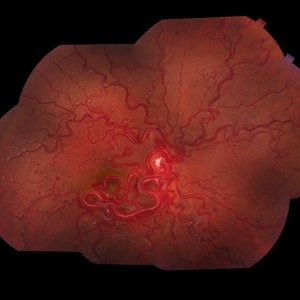

Wyburn Mason Racemose Angiomatosis

Color fundus montage of an 13-year-old female with arteriovenous malformation (Wyburn Mason Racemose Angiomatosis) affecting her right eye. The retinal arteriovenous malformation appears to be stable. She presented with NLP in the eye, strabismus, and peripheral retinal ischemia. She is at risk for neovascular complications; however, she is currently being treated with Sirolimus. Since she is on this systemically, there is no need to perform intraocular anti-VEGF injections or PRP laser. She also presented with optic atrophy affecting her left eye, secondary to chiasmal involvement of arteriovenous malformation. She has had a potential progressive visual field loss involving the temporal aspect of her visual field from the left eye. There is sector optic atrophy. Presumably, this is due to a compressive effect of her arteriovenous malformation on the nasal nerve fiber layer (corresponding to the temporal visual field) crossing to the right occipital cortex at the chiasm.

Photographer: Olivia Rainey

Imaging device: Topcon 50dx

Condition/keywords: arteriovenous malformation, color fundus photograph, color photo, montage, peripheral ischemia, Sirolimus